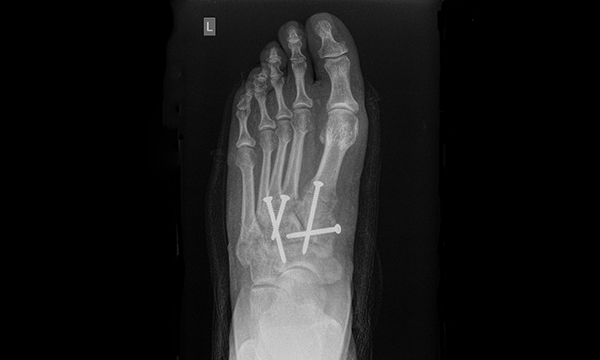

Injuries to the tarsometatarsal joint complex, also referred to as a Lisfranc injury, are relatively uncommon presentations to emergency departments (EDs), however accurate diagnosis is vital to prevent the risk of long-term disability. Advanced nurse practitioners (ANPs) must use a broad range of clinical skills to manage patients’ injuries effectively. A high level of suspicion, recognition of the clinical manifestations of Lisfranc injury and appropriate radiographic images are required to formulate a correct diagnosis.

This article describes Lisfranc injuries, revises the anatomy of the midfoot, and discusses diagnosis and management. It includes a case study to illustrate assessment and management of a patient who presented to an ED with a Lisfranc injury following a fall from a height and considers the diagnostic decisions and management options available to ANPs.